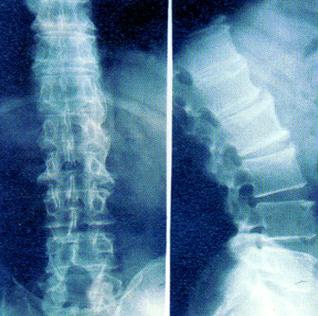

X线可以检查出脊柱关节变化也是诊断强直性脊柱炎的主要依据,脊柱的X线改变大多发生在骶髂关节改变之后,脊柱X线片早期可见骨质疏松,强直性脊柱炎中晚期出现方椎,脊椎间“骨桥”形成竹节一样的病变。贵阳治疗强直好医院

脊椎局部有小范围骨质硬化和破坏,这是早期X线的迹象,硬化开始于椎体的前角,有时候这种破坏很明显,致使受侵犯的椎体前角圆凸,方形椎体可持续存在。随着病变的发展,椎体前缘失去正常的凹陷,而出现特征性的方形椎体,这是由于发生在椎体前角的骨炎所引起的。有病期较长的患者,颈椎轴线变直,椎体呈方形,椎旁软组织钙化。推荐阅读:强直性脊柱炎会危害四肢关节吗? 贵阳治疗强直好医院

有些病变表现为椎间小关节变化为主,X线常显示为无脊柱韧带骨化,突出的表现是椎间小关节病变,表现为上下关节突之间的小关节间隙宽窄不匀,关节面破坏凹凸不平。关节面破坏较为严重的患者,上下关节突骨质增生较为明显,关节面硬化也很明显。病变发展到晚期,上下关节突完全或者部分骨性融合,关节突的周围大部分出现骨质增生硬化,有的合并小关节韧带骨化或椎旁韧带部分骨化,严重者可引起腰椎椎管狭窄。